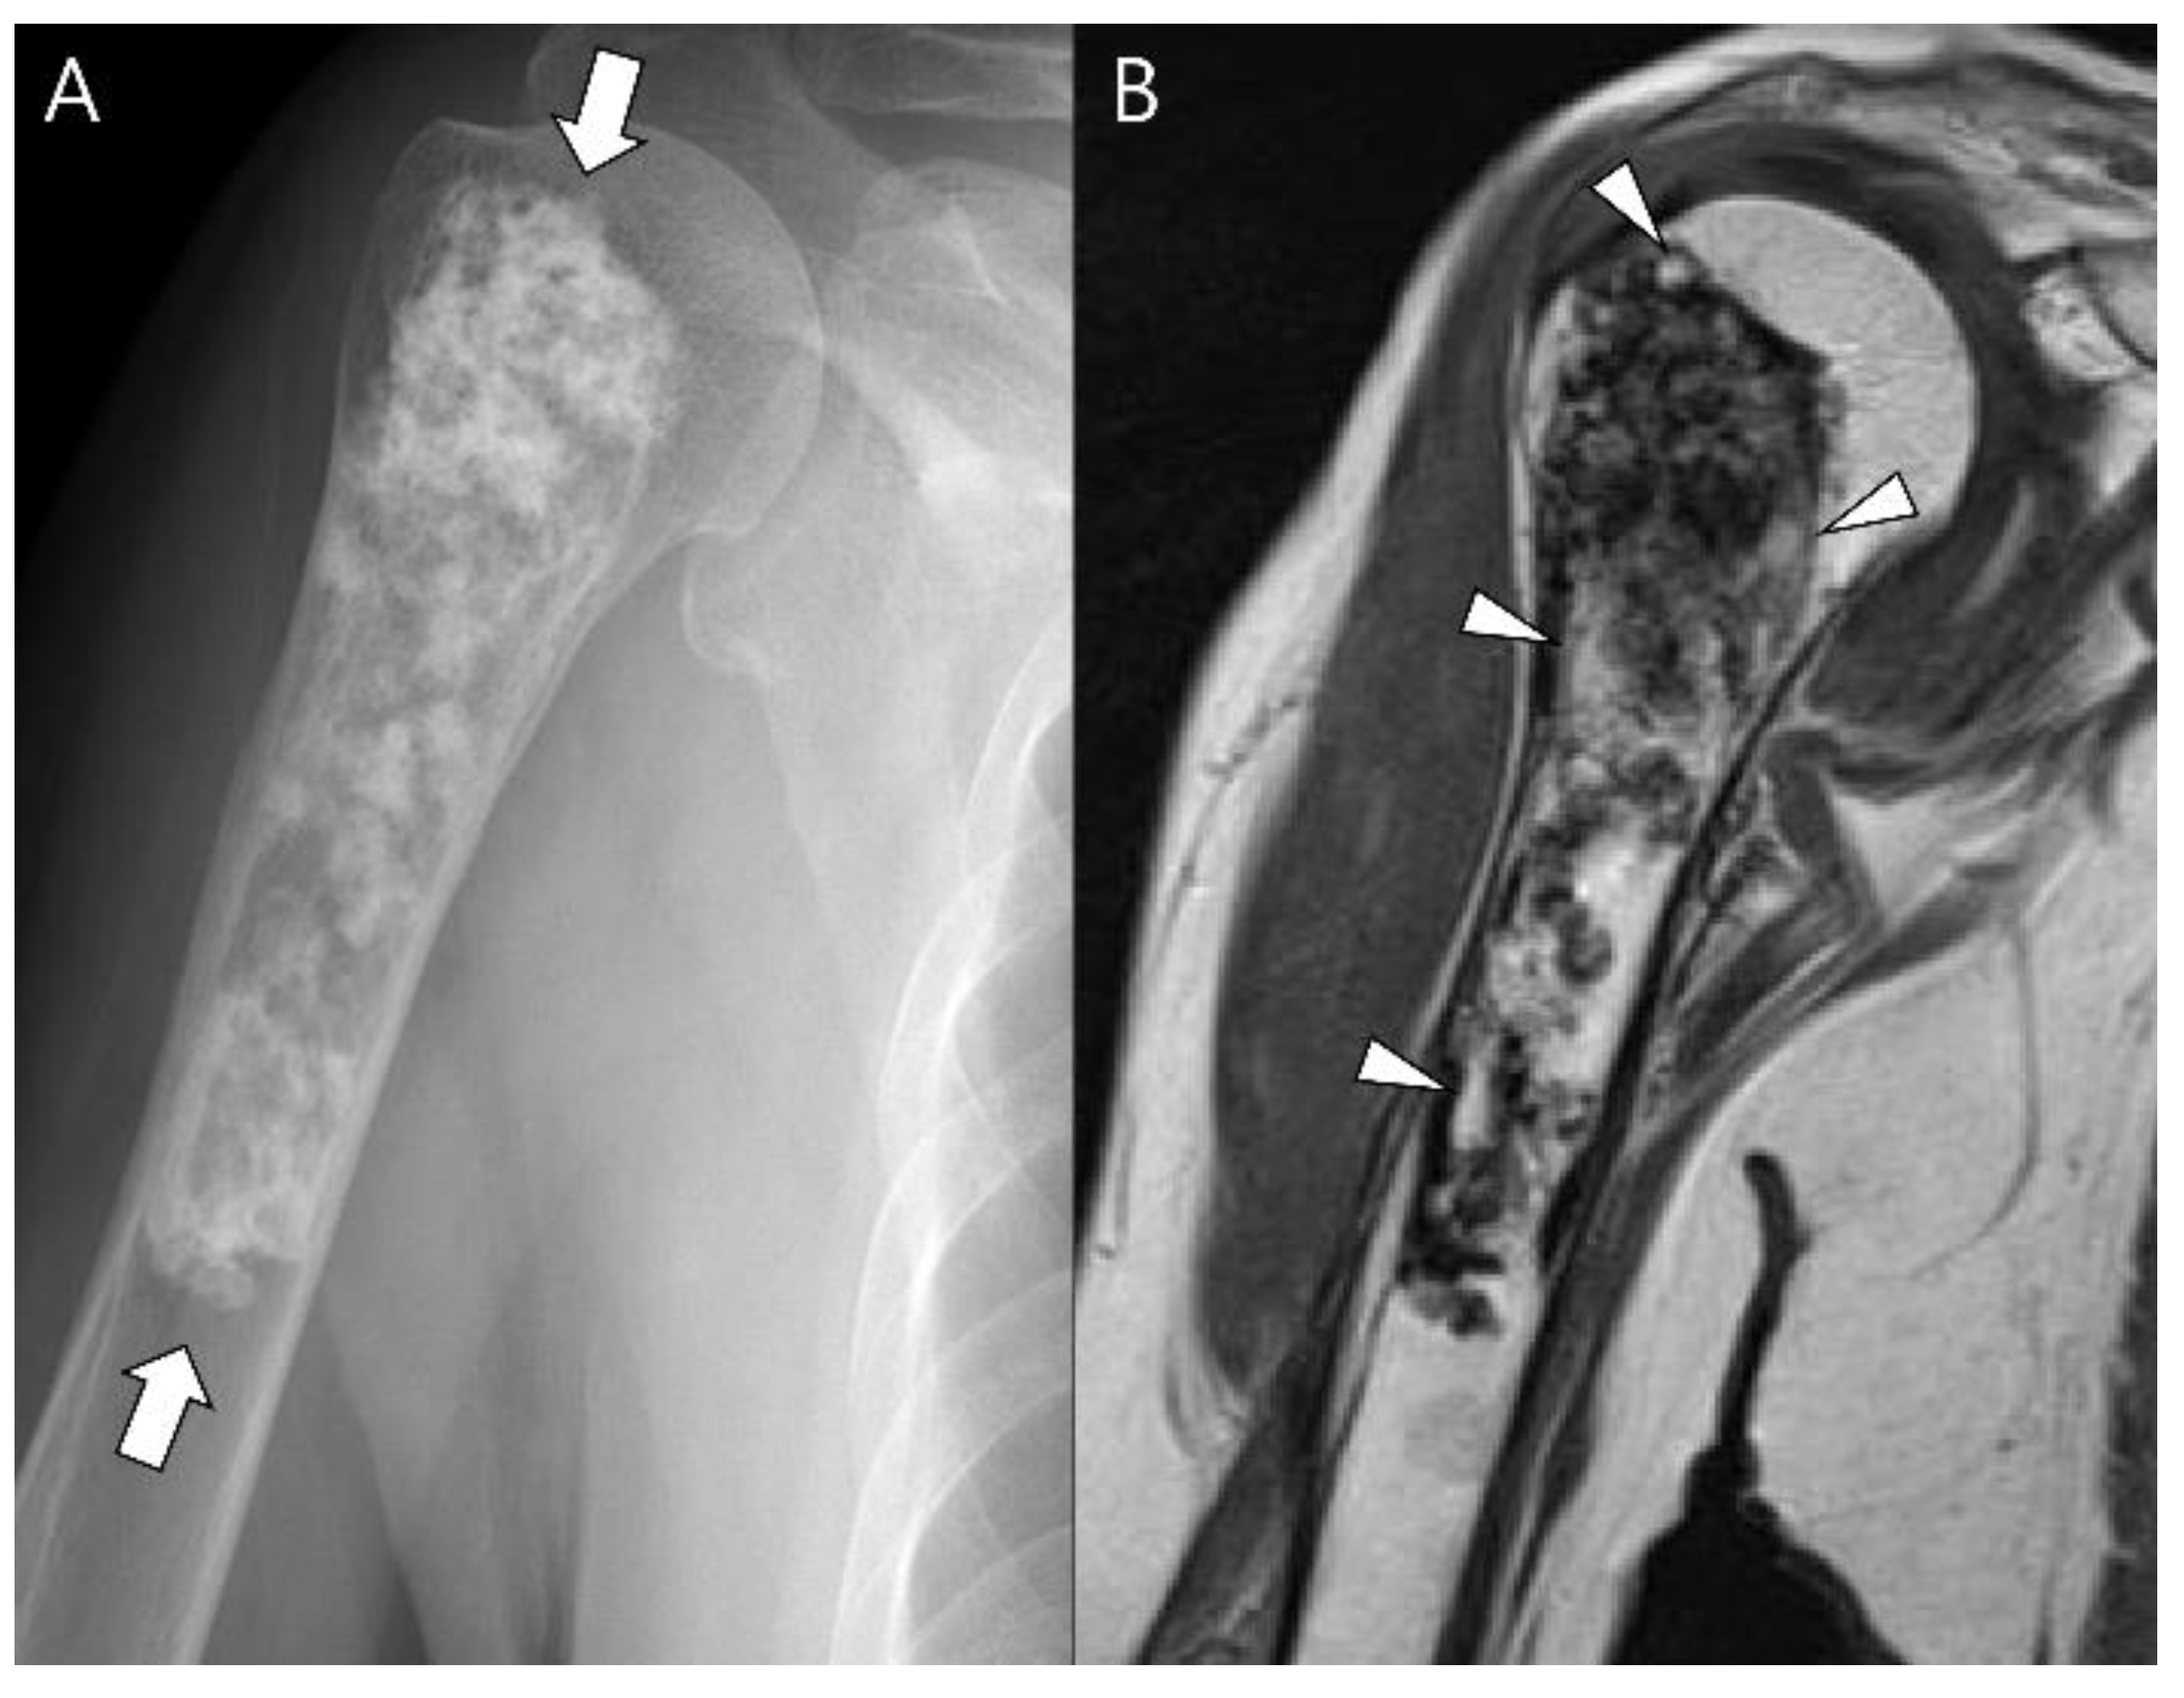

Figure 13.

Dedifferentiated chondrosarcoma of the humerus in a 54-year-old man. (A) Plain radiograph shows an extensive mixed lytic and sclerotic lesion in the humerus with endosteal scalloping (arrow). Note the chondral-type mineralization in the intramedullary cavity (arrowhead) and the densely osteoid-type mineralization at the juxtacortical area (curved arrow). (B) Axial CT scan also reveals the intramedullary chondral-type (arrowhead) and the juxtacortical dense osteoid-type (curved arrow) mineralization. (C) Coronal T2-weighted images with fat suppression show high signal intramedullary lesion (arrows) with osteoblastic extraosseous extension (curved arrow), suggesting a dedifferentiated component of osteosarcoma.